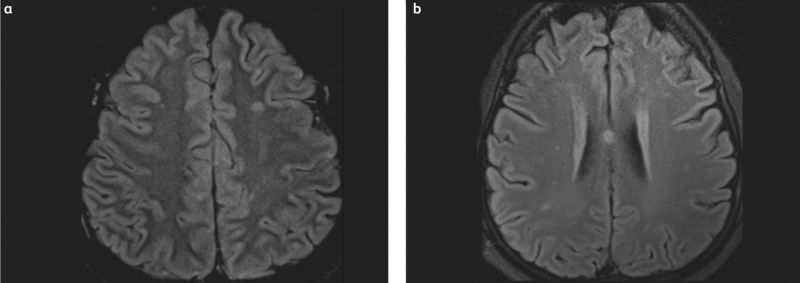

Figure 2: (a) Magnetic resonance imaging using fluid-attenuated inversion recovery shows multiple small bright lesions with areas of cortical involvement. (b) Magnetic resonance imaging using diffusion-weighted imaging demonstrates multiple bright lesions on both sides of the brain. Open access under terms of the Creative Commons License 4.0: https://creativecommons.org/licenses/by-nc-nd/4.0/. Original figures available at: https://doi.org/10.7861/clinmed.2022-0166